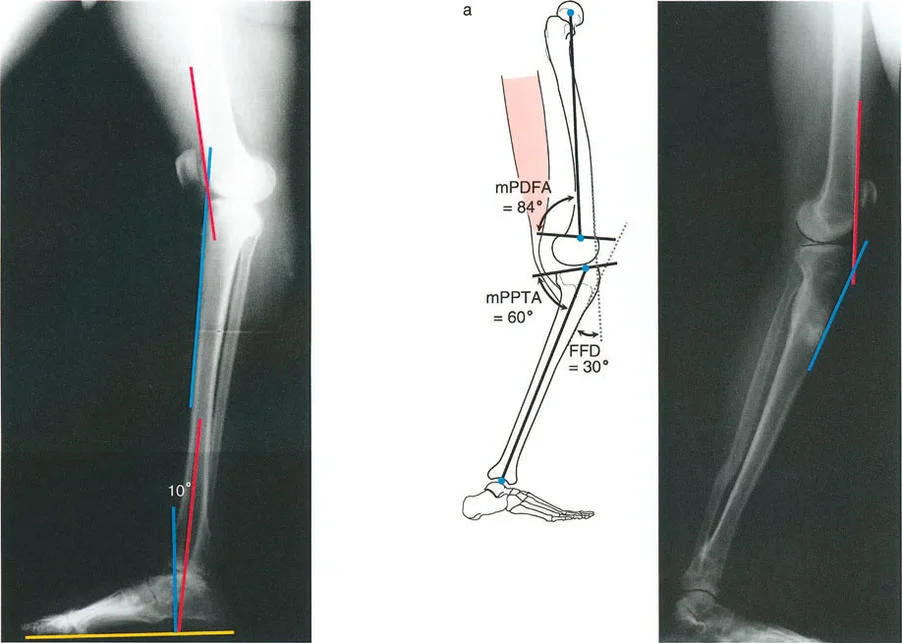

لنأخذ على سبيل المثال، تشوه الانحناء الأمامي (procurvatum) في الجزء البعيد من عظم الساق (الظنبوب) بمقدار 20 درجة. في تشوه الانحناء الأمامي (القمة الأمامية)، يميل السطح المفصلي البعيد لعظم الساق (plafond) إلى الأعلى (ظهريًا). لتحقيق قدم مستوية (plantigrade foot) على الأرض أثناء مرحلة الوقوف، يجب على المريض استهلاك مدى حركة البسط الظهري المتاح للكاحل فقط لاستيعاب العظم المنحني.

يتطلب التقدم الأمامي الطبيعي للجسم فوق قدم ثابتة ما لا يقل عن 10 درجات من البسط الظهري للكاحل خلال مرحلة دوران منتصف القدم. إذا استهلك تشوه الانحناء الأمامي بمقدار 20 درجة كل البسط الظهري المتاح لمجرد تسطيح القدم، فلن يتبقى أي بسط ظهري لمرحلة دوران منتصف القدم. سيؤدي ذلك إلى انحشار الحافة الأمامية للسطح المفصلي لعظم الساق البعيد مباشرة ضد عنق عظم الكاحل (talus).

النتيجة الحركية: نظرًا لأن عظم الساق لا يمكنه الدوران إلى الأمام فوق الكاحل، يجب على المريض تقصير طول خطوة الساق الطبيعية المقابلة بشكل مصطنع. علاوة على ذلك، للحفاظ على مركز الثقل يتحرك إلى الأمام دون السقوط، سيدفع المريض ركبة الساق المصابة بقوة إلى الخلف، مما يؤدي إلى فرط تمدد تعويضي (hyperextension) في الركبة من نفس الجانب. بمرور الوقت، يؤدي هذا الفرط الديناميكي في تمدد الركبة إلى تمدد المحفظة الخلفية ويمكن أن يؤدي إلى ألم شديد في الجزء الأمامي من الركبة، وانحشار الوسادة الدهنية، وأمراض الغضروف الهلالي.

2. وضع المفصل الثابت

في العديد من الحالات، يظهر تشوه العظم في منطقة الجدل أو المشاشة سريريًا على شكل انكماش مفصلي ثابت. هذا مفهوم حاسم في مبادئ بالي لتوجيه المفصل. يغير تشوه العظم بالقرب من المفصل خط المحور الميكانيكي ويغير اتجاه خط المفصل بالنسبة للأرض.

لنأخذ على سبيل المثال، تشوه الانحناء الأمامي (procurvatum) في الجزء القريب من عظم الساق. نظرًا لأن قمة التشوه أمامية، يميل سطح عظم الساق القريب (tibial plateau) إلى الخلف (مما يؤدي إلى زيادة في زاوية الظنبوب القريب الخلفية، أو pPTA). عندما يحاول المريض الوقوف مستقيمًا، قد تتمدد مفصل الركبة بالكامل تشريحيًا (0 درجات بين عظم الفخذ البعيد وعظم الساق القريب)، ولكن نظرًا لأن جدل الساق مقوس إلى الأمام، يظل الطرف الكلي مثنيًا بالنسبة للمحور الميكانيكي.

يظهر هذا سريريًا على شكل تشوه انثناء ثابت (Fixed Flexion Deformity - FFD) في الركبة. على عكس الجزء البعيد من عظم الساق، فإن مفصل الركبة لديه قدرة محدودة جدًا على فرط التمدد للتعويض عن هذا. نظرًا لأن الساق لا يمكن أن تستقيم بالكامل بالنسبة للأرض، لا يمكن للمريض تحقيق ملامسة كعب طبيعية أثناء الاتصال الأولي. بدلاً من ذلك، يظهرون "قدم مسطحة" أو "ملامسة أصبع القدم" عند الاتصال الأولي، مما يقلل بشكل كبير من امتصاص الصدمات، ويزيد من إجهاد العضلة الرباعية، ويقلل بشكل كبير من طول الخطوة في الجانب المصاب.

أمراض المستوى السهمي (الركبة الخلفية/الانحناء الأمامي - Recurvatum/Procurvatum):

يحدث التحميل غير الطبيعي أيضًا نتيجة للتضحية بحركة المفصل في المستوى السهمي. لننظر إلى تشوه الركبة الخلفية (recurvatum) في الجزء البعيد من عظم الساق (القمة الخلفية). لتسطيح القدم، يجب على المريض التعويض عن طريق ثني الكاحل بشدة (plantarflexion). يؤدي هذا الانثناء التعويضي إلى كشف الجزء الأمامي من قبة عظم الكاحل.

تظهر الأبحاث أن ما لا يقل عن 5 درجات من الركبة الخلفية مع الانثناء التعويضي يقلل من منطقة التلامس بين عظم الساق وعظم الكاحل بنسبة مذهلة تصل إلى 30%. وفقًا للفيزياء الأساسية (الضغط = القوة / المساحة)، فإن تقليل منطقة تحمل الوزن بنسبة 30% مع الحفاظ على نفس حمل وزن الجسم يزيد بشكل كبير من الضغط لكل وحدة مساحة على الغضروف المتبقي. يؤدي هذا الحمل المركز على الجزء الأمامي من مفصل الكاحل حتمًا إلى تآكل الغضروف الميكانيكي والتهاب مفصل الكاحل المبكر.